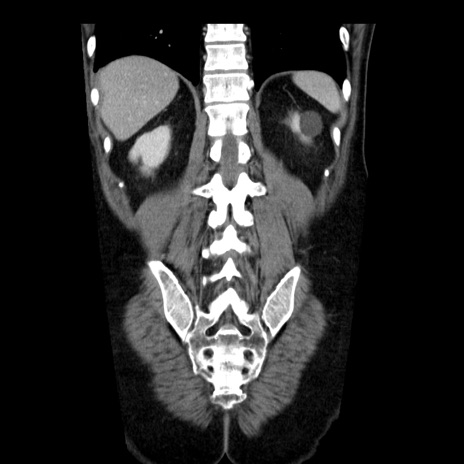

症例29(冠状断像)

【症例】40歳代男性

【現病歴】2日前から胃痛あり。徐々に周期的な激痛に変化した。本日になっても激痛があるため受診。

【身体所見】意識清明、BT 38-39℃台あり、腹部:膨満、やや硬、右下腹部に圧痛あり。

【データ】WBC 8500、CRP 23.26